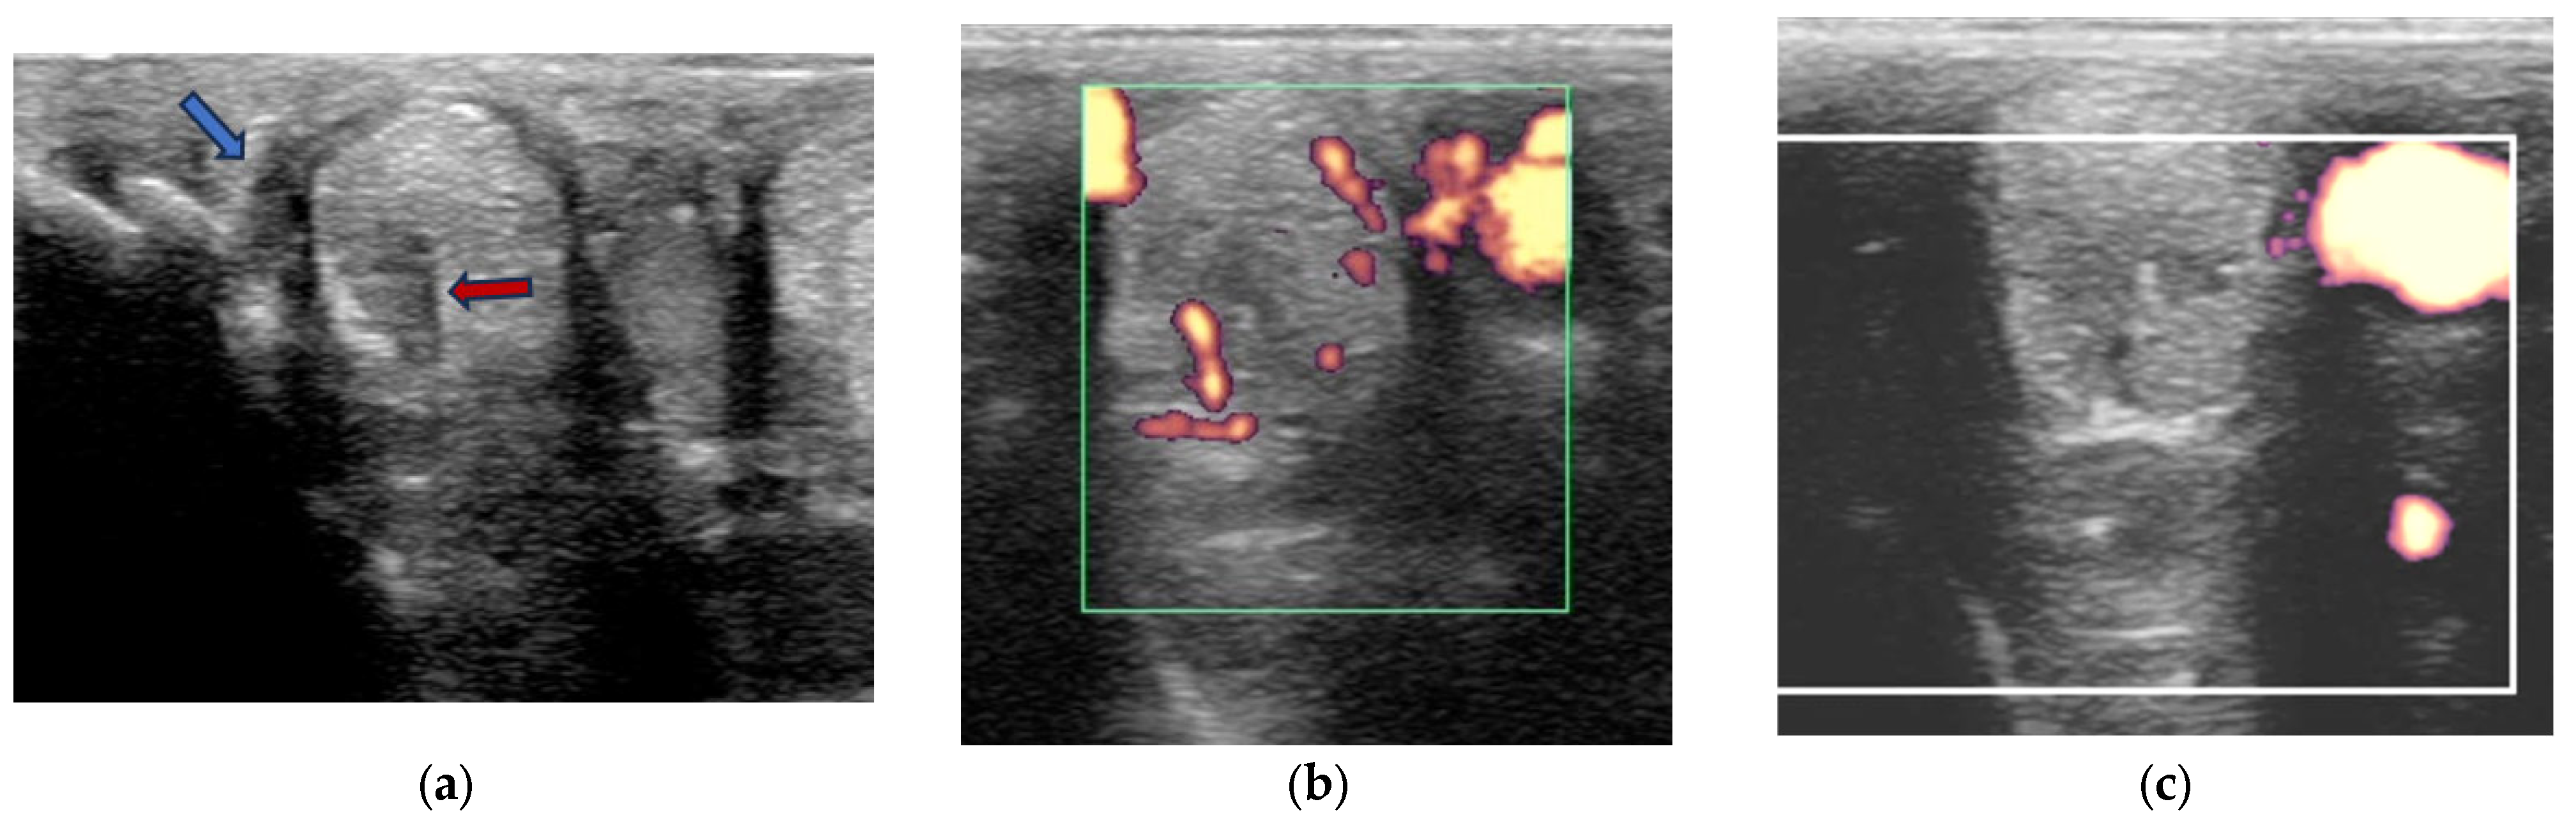

- Grade 0 = normal: uniform normal echogenicity; long linear parallel echoes in longitudinal images.

- Grade 1 = mild: less than 25% of the CSA of the ligament was hypoechoic with localised hypoechoic or anechoic lesions. Loss of linear echoes, reduced echogenicity in demarcated areas in longitudinal images.

- Grade 2 = moderate: Hypoechoic or anechoic regions occupying 25–50% of the CSA of the ligament. Loss of long linear parallel echoes in longitudinal images and mild to moderate changes at the enthesis such as irregularity of the bone surface or hyperechoic regions in the SL.

- Grade 3 = severe: Large anechoic and hypoechoic areas occupying >50% of the CSA of the ligament in transverse images. Hypoechoic or anechoic regions in longitudinal images and/or large hyperechoic regions (an avulsion or dystrophic mineralisation) in the SL and/or considerable irregularity of the bone surface at the enthesis.

2.3.2. Power Doppler Examination